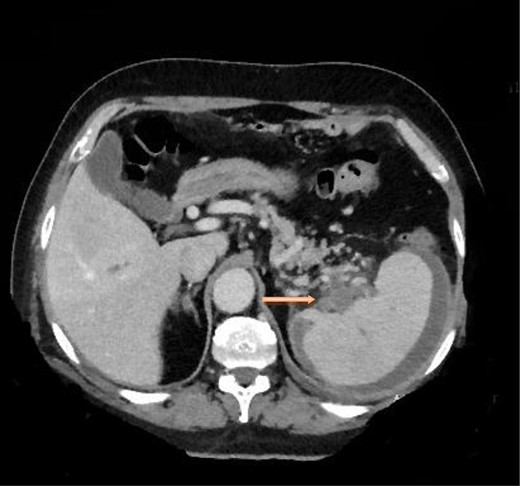

A computed tomography scan of the chest, abdomen and pelvis revealed splenic vein thrombosis (Fig. 1); and a filling defect in the lower lobar segmental branch of the right pulmonary artery consistent with acute segmental pulmonary embolism. A venous duplex scan of the extremities showed thrombosis of the left axillary and basilic veins (Figs 2 and 3). Echocardiogram was normal.

Computed tomography scan of the abdomen with evidence of splenic vein thrombosis at the splenic hilum.